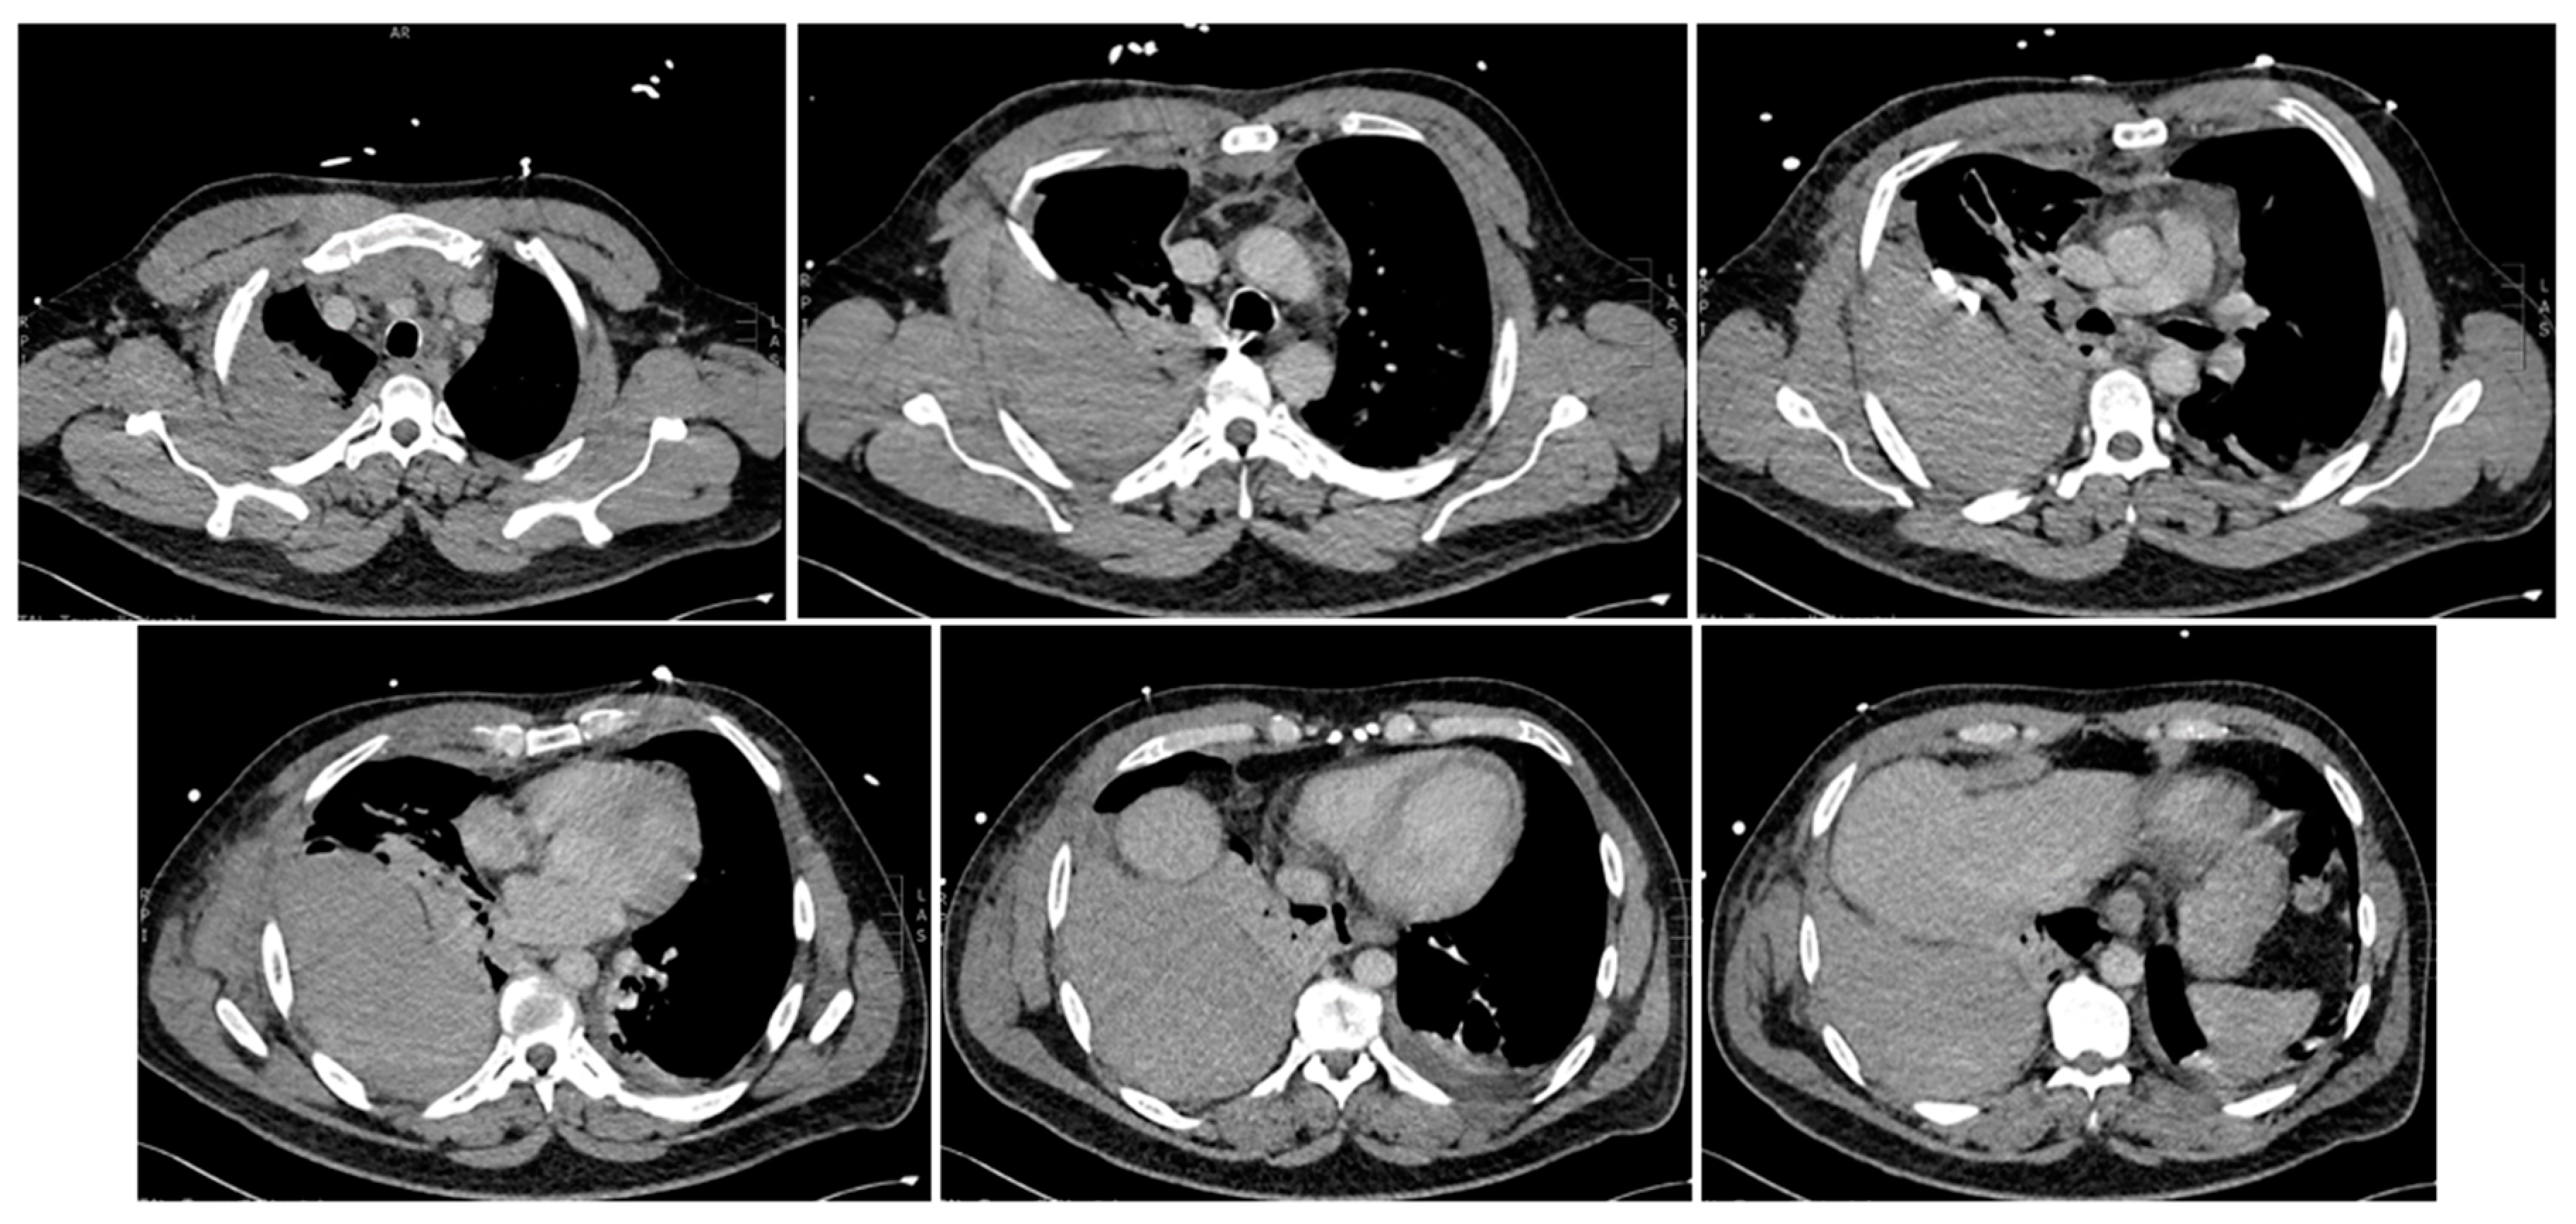

Arrival at the tertiary hospital happened two hours later, where he started to deteriorate at a faster pace. He remained afebrile, with a blood pressure of 97/49 mmHg, pulse rate of 112 bpm, and tachypneic at 26 respirations per minute with 92% saturation on 15 L of oxygen from a non-rebreather mask. The shock index was 1.2 at this time. A quick point-of-care venous blood gas showed a high anion gap metabolic acidosis with a raised lactate of 3.5. At this point, he entered a hemorrhagic shock along with a respiratory compromise secondary to the expanding hemothorax causing an external restrictive effect on his lung parenchyma. He was quickly sent for a repeat CT chest study without contrast (Figure 3) and was given one unit of packed red blood cells along with 2 g of fibrinogen concentrate. Shortly after, he was being sedated for a selective angiography of his right intercostal arteries and embolization of areas of bleeding.

Figure 2. Multiphase CT scan with contrast of chest progressing from superior to inferior. Multiple bilateral rib fractures of 2nd to 6th ribs bilaterally. Moderate right-sided hematoma seen in posterior right extra-pleural space with contrast extravasation seen at the posterior right 3rd and 4th intercostal space suggestive of an active bleed. Right hemothorax. Anterosuperior mediastinal hemoatoma. Collapse consolidation in lung bases. Ground glass opacities with smooth septal thickening in both lung apices. Abdominal organs (not shown) are unremarkable.

Figure 3. Multiphase CT scan without contrast, arterial and delayed phases, progressing from superior to inferior, compared to previous CT. Increasing size of large right extra-pleural hematoma with multiple sites of active bleeding from intercostal arteries. Moderate-sized right hemothorax seemingly enlarging. Superior mediastinal and right chest wall hematoma.